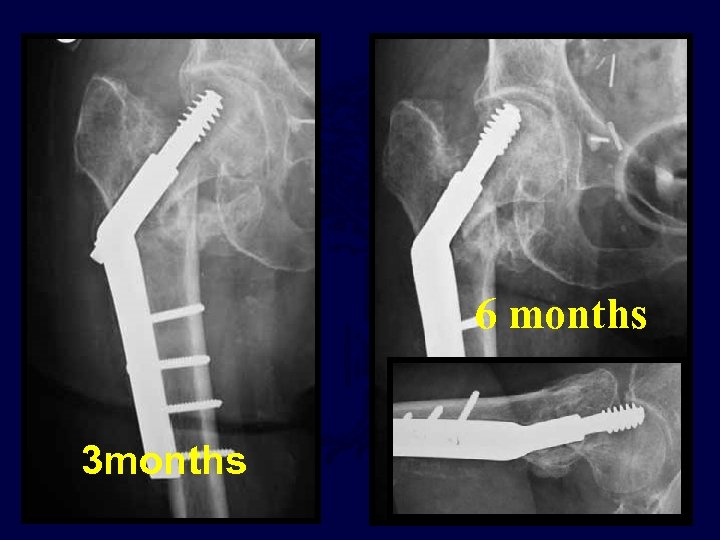

6 months 3 months

Post op

The TAD was acceptable but the reduction was grossly short